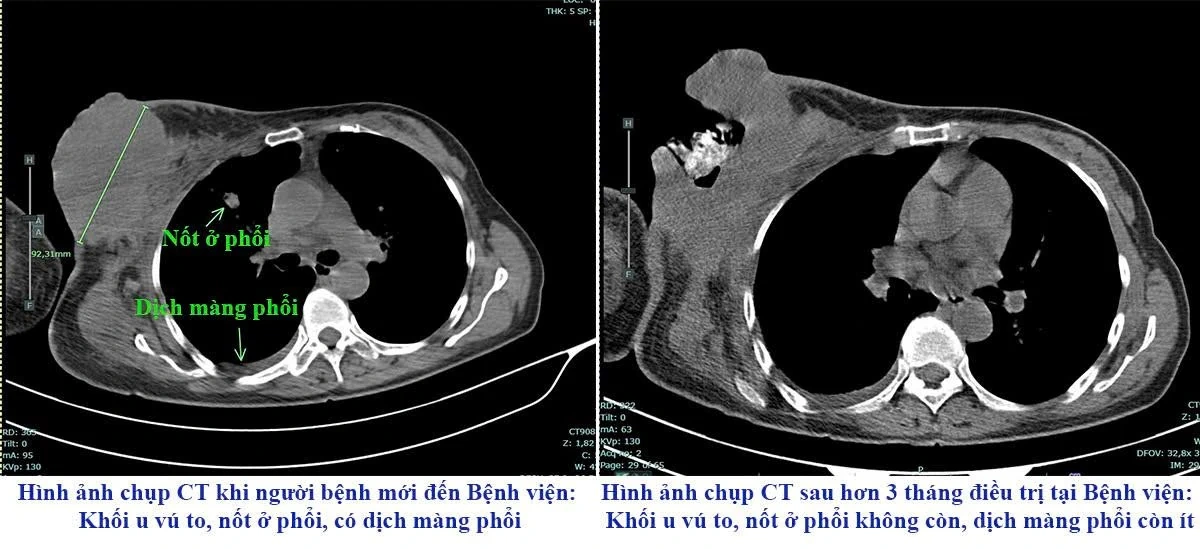

Tháng 8/2024, người bệnh đến Bệnh viện Đa khoa tỉnh trong tình trạng suy kiệt, khối u vú phải kích thước lớn, vỡ loét chảy dịch, thâm nhiễm rộng tổ chức da vùng ngực, di căn hạch và di căn xa nhiều nơi. Với trường hợp này điều trị và chăm sóc rất khó khăn.

Hình ảnh chụp CT trước và sau điều trị của người bệnh.